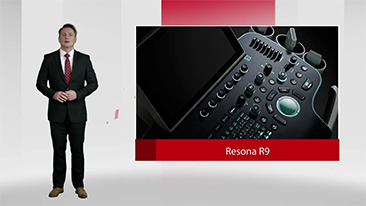

Solusi Pencitraan Umum Resona dari Mindray membantu para dokter mewujudkan diagnosis dan hasil pengobatan yang lebih akurat dan efisien melalui pemerik aplikasi subdivisi yang komprehensif dan alat bantu aplikasi klinis yang efisien.